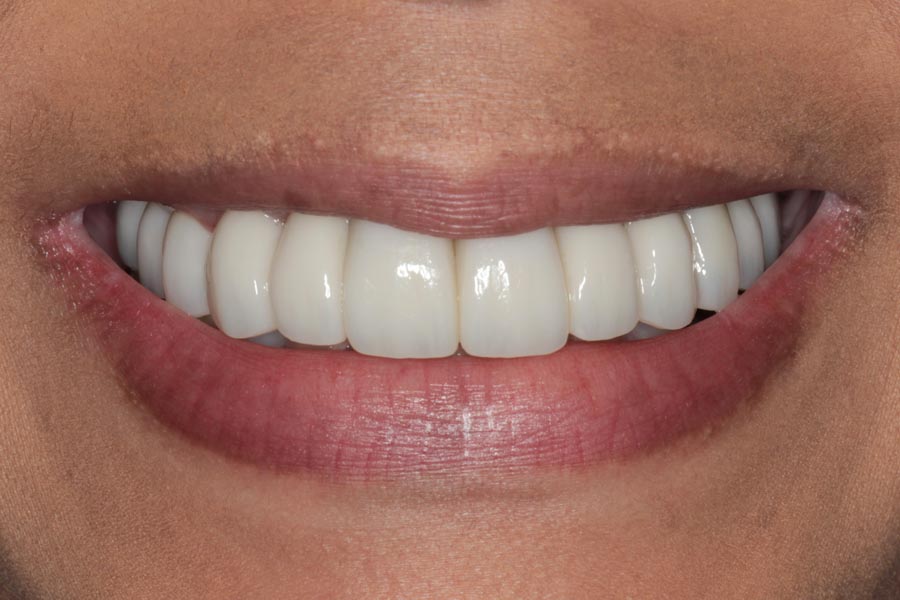

Smile GalleryImplant RestorationsFull Mouth Implant Restoration Full arch zirconia implant bridge (full smile) 1 of 37 Pre-op full smile Pre-op lips retracted Pre-op panoramic x-ray Extraction of strategic teeth Placement of implants Extraction of some remaining teeth after verification of adequate implant stability Occlusal view Post-op panoramic x-ray Immediately fabricated provisional restoration (tissue side view) Immediately fabricated provisional restoration (occlusal side view) Immediate provisional delivered on day of surgery Immediate provisional 2 weeks later Scalloped tissue developed from the provisional at 2 weeks Jig used for making a master impression Provisional in place (full smile) Provisional in place (lips retracted) Provisional in place (right side) Provisional in place (left side) Wax try-in (full smile) Wax try-in (right side full smile) Wax try-in (left side full smile) Wax try-in (full face, lips together) Wax try-in (full smile) Wax try-in (right side) Wax try-in (left side) Wax try-in (lips retracted) Full arch zirconia implant bridge on master cast (frontal view) Full arch zirconia implant bridge on master cast (occlusal view) Implant positions and soft tissue representation on master cast (occlusal view) Soft tissue representation on master cast (frontal view) Full arch zirconia implant bridge (tissue side view) Soft tissues on day of delivery (occlusal view) Soft tissues on day of delivery (frontal view) Full arch zirconia implant bridge delivered (lips retracted) Full arch zirconia implant bridge (lips retracted, close up) Post treatment panoramic x-ray Full arch zirconia implant bridge (full smile)